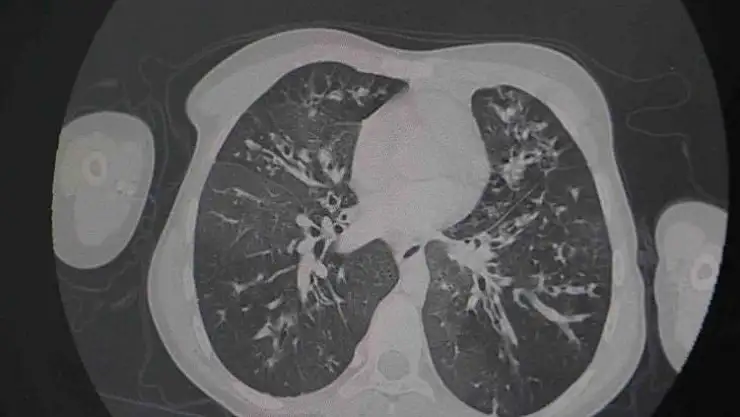

Diyarbakır’da, Gazi Yaşargil Eğitim ve Araştırma Hastanesi’nde Çocuk Göğüs Hastalıkları Yan Dal Uzmanı Dr. Özge Meral, "Kistik fibrozis, genetik geçişli bir hastalıktır. Dünya çapında ve ülkemizde de oldukça sık karşılaştığımız bir durum. Bizim için en önemli nokta ne kadar erken tanı koyabilirsek o kadar gelişecek olan akciğer hasarının önüne geçebiliyoruz" dedi.

"Bizim için en önemli nokta ne kadar erken tanı koyabilirsek o kadar gelişecek olan akciğer hasarının önüne geçebiliyoruz" diyen Dr. Meral, "Bu nedenle de zaten 2015 yılından itibaren topuk taramayla Sağlık Bakanlığımız tarafından yeni doğan bebekler taranmakta. Biz de daha çok taramada pozitif gelmiş olan hastalara sonraki aşamada değerlendirme ve tanı koyma kısmında devreye giriyoruz” dedi.

Kistik fibrozis hastalığının en sık akciğer tutulumu yapmakla birlikte mide-bağırsak sistemi ve pek çok sistemleri de tutabilen bir hastalık olduğunun altını çizen Meral, “Biz hastalara ne kadar erken tanı koyarsak bu hastalığın hem ilerlemesinin önüne geçmiş oluyoruz. Takibimizde olan hastaların da uygun şekilde tetkiklerini yaparak koruyucu önlemler alıp en ufak bir enfeksiyon durumunda erken müdahale ederek akciğer hasarının da önüne geçmiş oluyoruz” ifadelerine yer verdi.

Hastaların belirli aralıklarla mutlaka takiplerinin yapılması, uygun şekilde örneklemelerin alınmasının çok önemli olduğunu dile getiren Meral, “Bu aşamada belirli aralıklarla görüntüleme yapıyoruz. Hastaların örneklemelerini alıyoruz. Burada bizim için önemli olan hastaların balgam tahlillerini yapabilmek. Bu tahliller neticesinde enfeksiyonlar olabilir. Bu hasta grubunun en önemli sorunu zaten dirençli enfeksiyonlar olmasıdır. Bu dirençli enfeksiyonlar için erken dönemde tedaviye başladığımız zaman daha da direnç kazanmasının önüne geçmiş oluyoruz. Bu nedenle bu hastaların belirli aralıklarla mutlaka takiplerinin yapılması, uygun şekilde örneklemelerin alınması önemlidir. Biz de zaten hastanemizde bu hastalarımızın takibi için ayrı bir oda ve birim oluşturduk” diye konuştu.